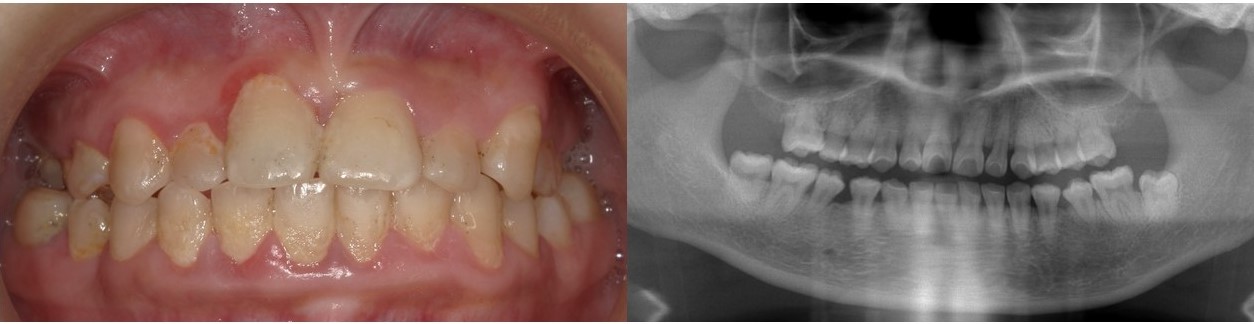

スポーツドリンクなどのイオン飲料は、身体によいものとしてのイメージが定着しており、暑い時期などには特に多量に摂取される機会もあるかと思います。一方で、イオン飲料には、多量の糖分が含まれていることがあまり意識されていません。特に、ペットボトルから摂取する際には、

無意識のうちに回数が多くなる傾向にあります。そのため、断続的であっても口腔内のpHが低下する総時間が増加することで脱灰の時間が増加して、多くの歯にう蝕が生じてしまいます(図5)。そもそも、水分補給には水やお茶を中心にすることが重要であり、イオン飲料を摂取する際には、就寝前は必ず避けるように指導してください。

(図5)イオン飲料によるう蝕の一例(13歳男子)